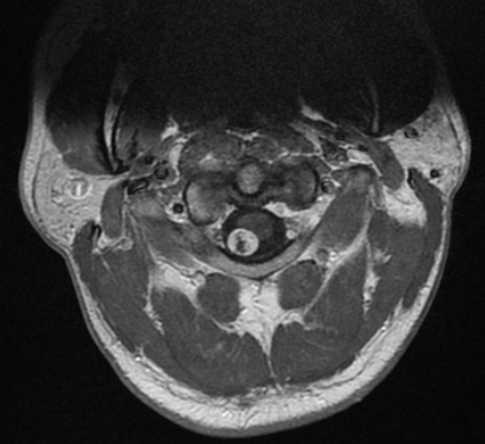

Control postoperatorio inmediato. Corte axial con gadolinio a la altura del atlas.